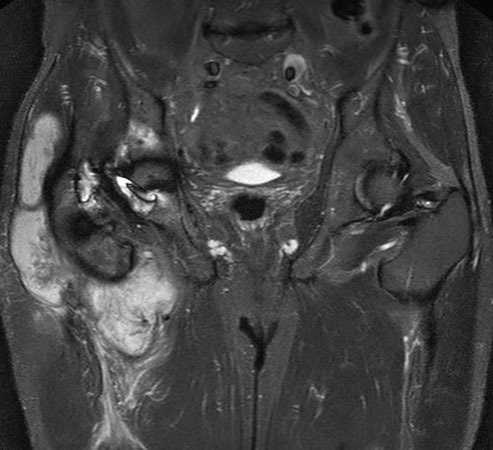

Hip imaging with metal implant using MARS at 1.5T

**Only for use with MR Safe or MR Conditional Implants by strictly following the Instructions for Use.